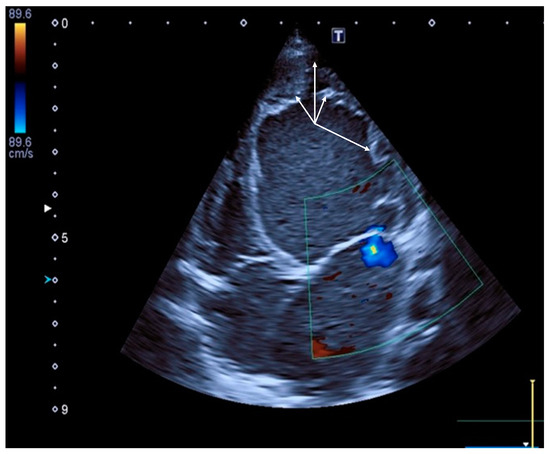

2.1. Clinical Case